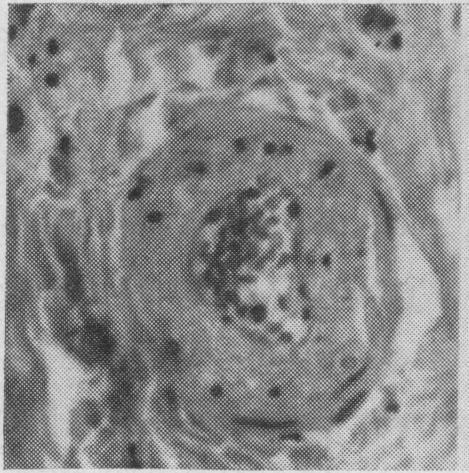

Radiation fibrosis of pericardium, with cardiac tamponade; case report with post-mortem studies and review of literature.

https://cdn.ncbi.nlm.nih.gov/pmc/blobs/8521/1831393/8e02dd1f7ea1/canmedaj00812-0093-a.jpg